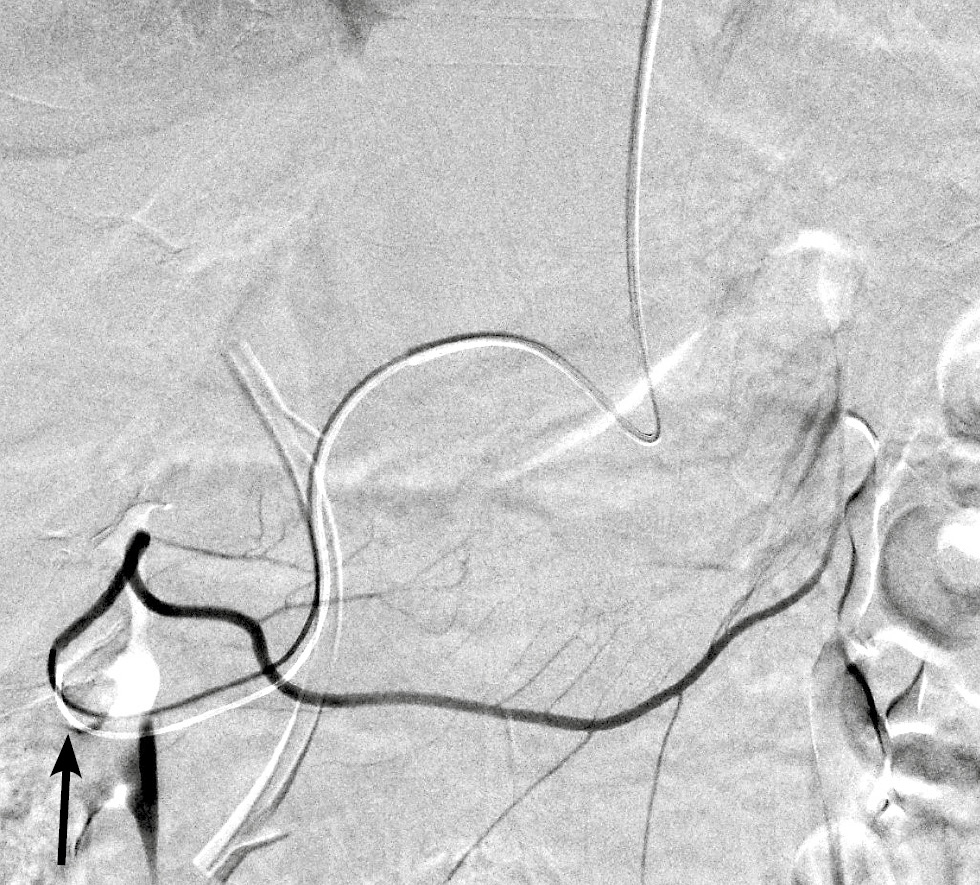

В обеих группах после выполнения ангиографии верхней брыжеечной артерии и чревного ствола (рис. 1) с помощью микрокатетера селективно катетеризировали правую желудочно-сальниковую артерию (рис. 2). С целью тотальной эмболизации опухоли поджелудочной железы и предотвращения нецелевой эмболизации применяли перераспределительную технику вмешательства: через упомянутый выше микрокатетер в правую желудочно-сальниковую артерию дистальнее отхождения всех кровоснабжающих опухоль ветвей последовательно имплантировали 2–3 толкаемые спирали (рис. 3), после чего вводили смесь липиодола в дозе 5 мл и гемцитабина в дозе 1000 мг (рис. 4).

Рис. 1. Ангиограмма общей печёночной артерии: левая печёночная артерия (белая стрелка) и гастродуоденальная артерия (чёрная стрелка).

Fig. 1. Angiogram of the common hepatic artery: left hepatic artery (white arrows) and gastroduodenal artery (black arrow).